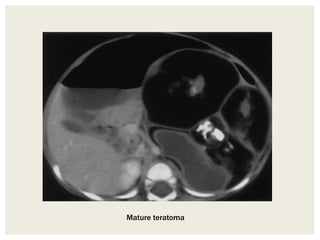

Teratomas

• Congenital neoplasms containing components of all three

germ layers.

• Range from benign, mature, well-differentiated cystic lesions

to immature, poorly differentiated lesions with solid

components and malignant transformation.

• As a result they can contain a large variety of tissue types

including: fat, cystic spaces due to mucous production or

other exocrine products, soft-tissue and calcification including

teeth. Fat-fluid levels may be seen. Sometimes a dermoid

plug is identifiable as soft tissue mural nodule projecting into

the cyst.

• The incidence of malignant degeneration is rare (<1%), and

usually occurs in dermoid plug in postmenopausal females

Mature teratoma